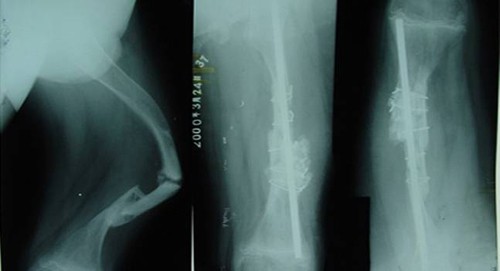

Cậu bé "búp bê sứ" có đôi chân biến dạng nghiêm trọng

Do mắc hội chứng "búp bê sứ" hiếm gặp mà cậu bé Tiểu Lưu thường xuyên bị gãy xương, điều này đã dẫn tới tình trạng đôi chân cậu bị cong vênh. Hội chứng xương giòn là loại bệnh khiến người bệnh thường bị gãy xương, vì vậy, mọi người ví những bệnh nhân này là “búp bê sứ”. Cậu bé 11 tuổi tên là Tiểu Lưu sống tại Hà Bắc, Trung Quốc cũng là một trong số những người bị mắc bệnh này. Từ khi còn nhỏ, xương chân của Tiểu Lưu đã bị gãy không biết bao nhiêu lần. Đôi chân của em cũng vì thế mà chịu nhiều di chứng và biến dạng nghiêm trọng theo. “Búp bê sứ” là kết quả của sự xuất hiện các gen bất thường, gây ảnh hưởng đến tổng hợp mô liên kết. Dù chỉ có một vết thương nhỏ, bệnh nhân cũng có thể bị gãy xương. Biểu hiện của bệnh là xuất hiện nhiều vết nứt gãy ở xương, đặc biệt là với những người mắc bệnh bẩm sinh. Nhiều lần bị gãy xương như vậy sẽ khiến chiều cao của bệnh nhân tụt giảm, tuy nhiên, qua tuổi dậy thì bệnh cũng có xu hướng giảm dần. Ngày nay, trong điều kiện trình độ y học còn giới hạn, vẫn chưa có dụng cụ chuyên môn để chữa bệnh cho Tiểu Lưu. Vì vậy, đội ngũ bác sĩ đã thiết kế ra một thiết bị chuyên dụng để điều trị riêng cho Tiểu Lưu.

Quá trình phẫu thuật chủ yếu là để làm thẳng phần xương bị biến dạng, sau đó là cấy một ống nẹp chuyên dụng vào chân để cố định. Cách làm này tuy có thể giữ vững được vùng xương gãy nhưng cũng không thể đảm bảo cho vùng xương bên dưới hay bên trên nẹp không bị gãy. Mặc dù hiện nay y học thế giới vẫn chưa tìm ra phương hướng điều trị triệt để căn bệnh kỳ lạ này tuy nhiên tình trạng của cậu bé Tiểu Lưu cũng đã có chiều hướng tích cực hơn sau đợt điều trị kéo dài. Vậy là sau 3 năm, cậu bé Tiểu Lưu 14 đã có thể đi lại bình thường và tham gia các hoạt động nhẹ. Ngoài ra, gia đình Tiểu Lưu còn cho biết, thành tích học tập của em rất tốt, em đã đạt được giải nhất cấp quận.

Tình trạng của Tiểu Lưu sau 3 năm điều trị. |